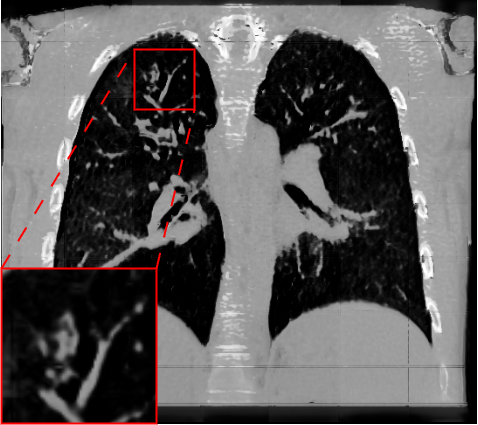

Fig. 2 presents a visual comparison of lung coronal sections from different models. The model using L1 loss results in blurred images, with particularly poor bone reconstruction. In contrast, the MedicalNet-based model produces sharper images but introduces artifacts in anatomical areas. Models based on AFP loss offer visually appealing results, with well-reconstructed anatomical bones and lung tissue. Additionally, only NaviAirway and HAL methods provide detailed bronchial reconstruction, as highlighted in the zoomed-in section.

To handle memory constraints during training and inference, we used a patch-based strategy. We experimented with multiple patch sizes, including and , and also used nnU-Net’s default adaptive windowing strategy (e.g. for thoracic cases). While larger patches provide more contextual information and generally improve reconstruction quality, the overall performance did not differ substantially from nnU-Net’s dynamic patching. Some visible artifacts in Fig.2 result from patch combination, especially in regions not covered by the segmentation network used for AFP supervision. For instance, when the AFP loss relies on the NaviAirway model, artifacts often appear outside the lung fields, as the network lacks anatomical guidance in those regions. However, these artifacts are purely visual and do not affect the downstream segmentation results or the quantitative metrics reported, which are detailed in the upcoming paragraph.

Table 1 presents a quantitative evaluation of the model’s performance on lung MR to CT synthesis, based on the MAE, SSIM, Dice score, and NSD between synthesized and ground truth CT images. The adapted nnU-Net trained with L1 loss delivers the best performance on intensity-based metrics, yielding a MAE of 48.72 and an SSIM of 0.837. In contrast, other models based on perceptual loss or AFP loss achieve average MAE results but maintain competitive SSIM values, for example, the AFP loss with TotalSegmentator embeddings achieves an SSIM of 0.828. In the context of airway segmentations using the NaviAirway pipeline, the adapted nnU-Net models with AFP loss from NaviAirway and HAL’s embeddings deliver the best performance, achieving the highest Dice score of 0.584 and NSD value of 0.723. Conversely, models employing L1, perceptual, or AFP loss with TotalSegmentator’s embeddings yield poorer results, lacking precise bronchial reconstruction. The GAN-based SPADE method generally underperforms compared to nnU-Net, but adding AFP loss to SPADE enhances its performance. These metrics align with qualitative analysis from Fig. 2 and Fig. 3, with the models using AFP loss delivering the best performance in airway reconstruction.